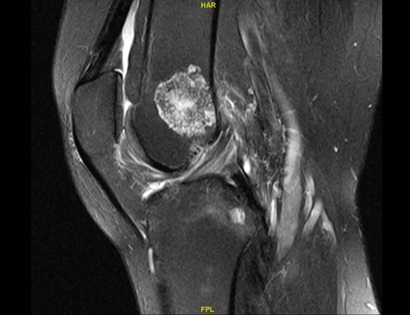

Example of MRI showing an Enchondroma